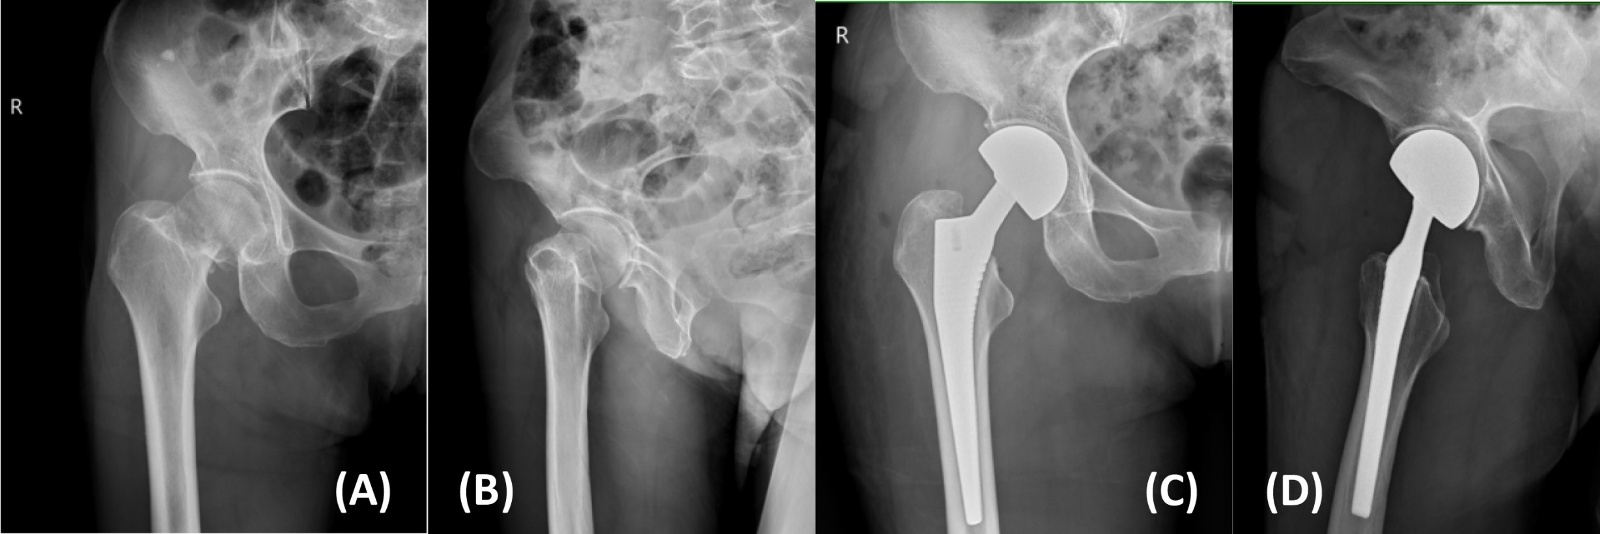

典型病例影像学表现见图1~5图1为70岁女性右侧股骨颈骨折(Garden Ⅲ型)患者,改良hardinge入路半髋关节置换术前X线示骨折断端部分错位,术后X线示假体位置良好;图2为85岁女性左侧股骨颈骨折(Garden Ⅲ型)患者,术后X线示假体位置良好;图3为83岁男性右侧股骨颈骨折(Garden Ⅲ型)患者,术后假体位置满意;图4为91岁男性左侧股骨颈骨折(Garden Ⅳ型)患者,术后假体匹配良好;图5为75岁女性左侧股骨颈骨折(Garden Ⅲ型)患者,术后假体位置正常,股骨近端微裂予钢丝捆扎固定。

Figure 4. X-rays before and after modified hardinge approach hemiarthroplasty in a 91-year-old male patient with left femoral neck fracture (Garden IV type) (A), (B). Before operation; (C), (D). After operation

4. 为91岁男性左侧股骨颈骨折(Garden IV型)患者改良hardinge入路半髋关节置换手术前后X线片(A)、(B) 术前;(C)、(D) 术后